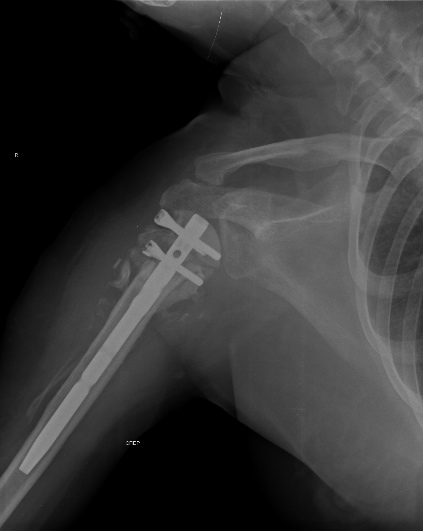

Пошли на операцию, будучи готовыми как к фиксации, так и к протезированию.

Головка с краев была неполная, но для двух винтов места хватило. Сделали

что-то вроде гемиартропластики собственной головкой. Бугорки фиксировали,

как при эндопротезировании.

Снимки вот.